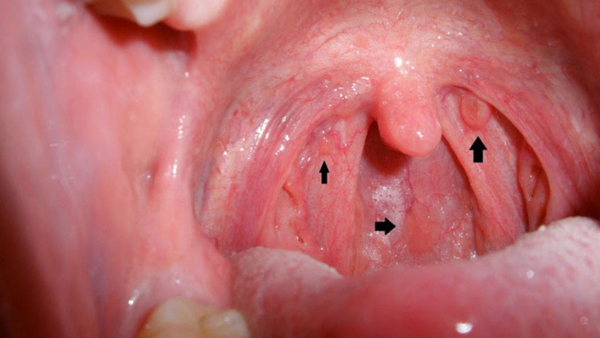

Amidan là các tuyến lympho nằm ở hai bên vòm họng, có chức năng bảo vệ cơ thể khỏi các tác nhân gây bệnh từ bên ngoài. Khi amidan bị nhiễm trùng, sẽ gây ra tình trạng viêm amidan. Bệnh có thể do vi khuẩn, virus hoặc các tác nhân khác gây ra.

- Sưng amidan: Amidan bị sưng đỏ, có thể thấy mủ trắng hoặc các đốm trắng trên amidan.